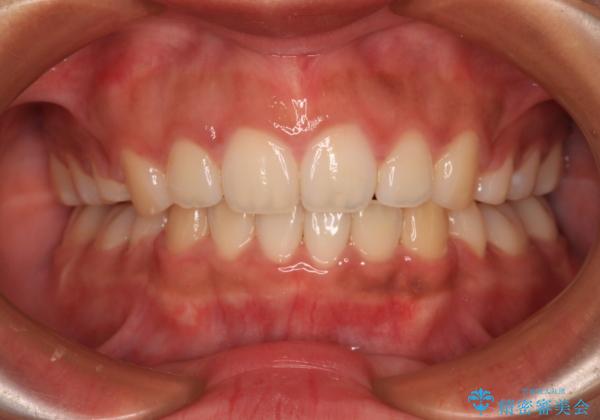

口元の突出感を改善するため、上下左右第一小臼歯4本の抜歯を行い、ワイヤー装置による矯正治療を行うこととしました。

舌の突出癖により上下前歯は非接触であり、非常に前方に飛び出している状態でした。

舌のトレーニングをしっかりと行っていただき、口の閉じやすい歯並びに仕上げることができました。